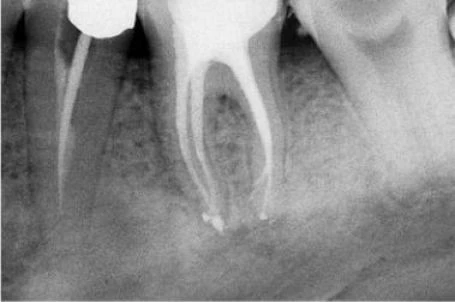

–  Ống tủy xa thứ 2 thỉnh thoảng được thấy ở 1 chân riêng biệt ở phía xa trong. Nó hơinhỏ hơn và nằm ở phía gần chân răng xa ngoài (hình 11.110).

Hình 11.110. A. Một vùng hơi cản quang trong vùng chẽ R36 vì chân xa ngoài. Dễ dàng nhận ra phần laminadura bao quanh chân răng này và hình ảnh ống tủy. B. Hình ảnh răng cối lớn một dưới sau khinhổ ra. C. Phim sau điều trị R46 với 2 chân xa và 2 ống tủy xa.